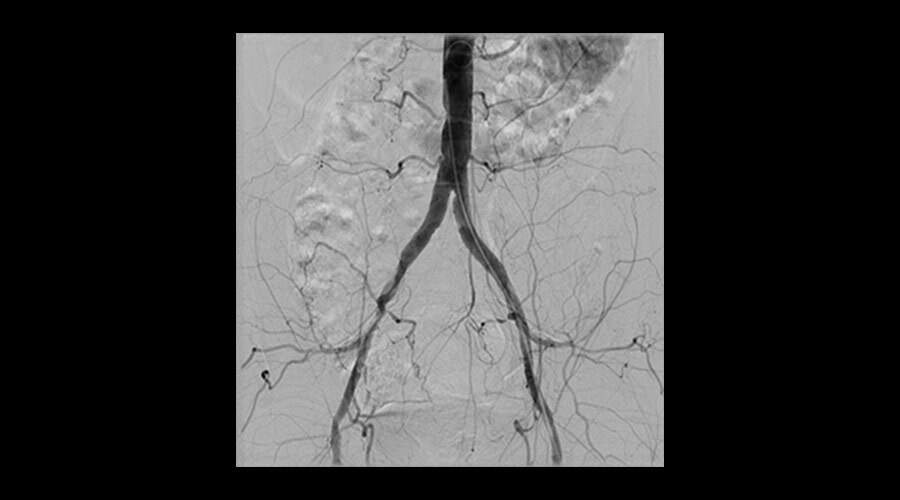

Klinik Görüntüler

-

Aortic procedure